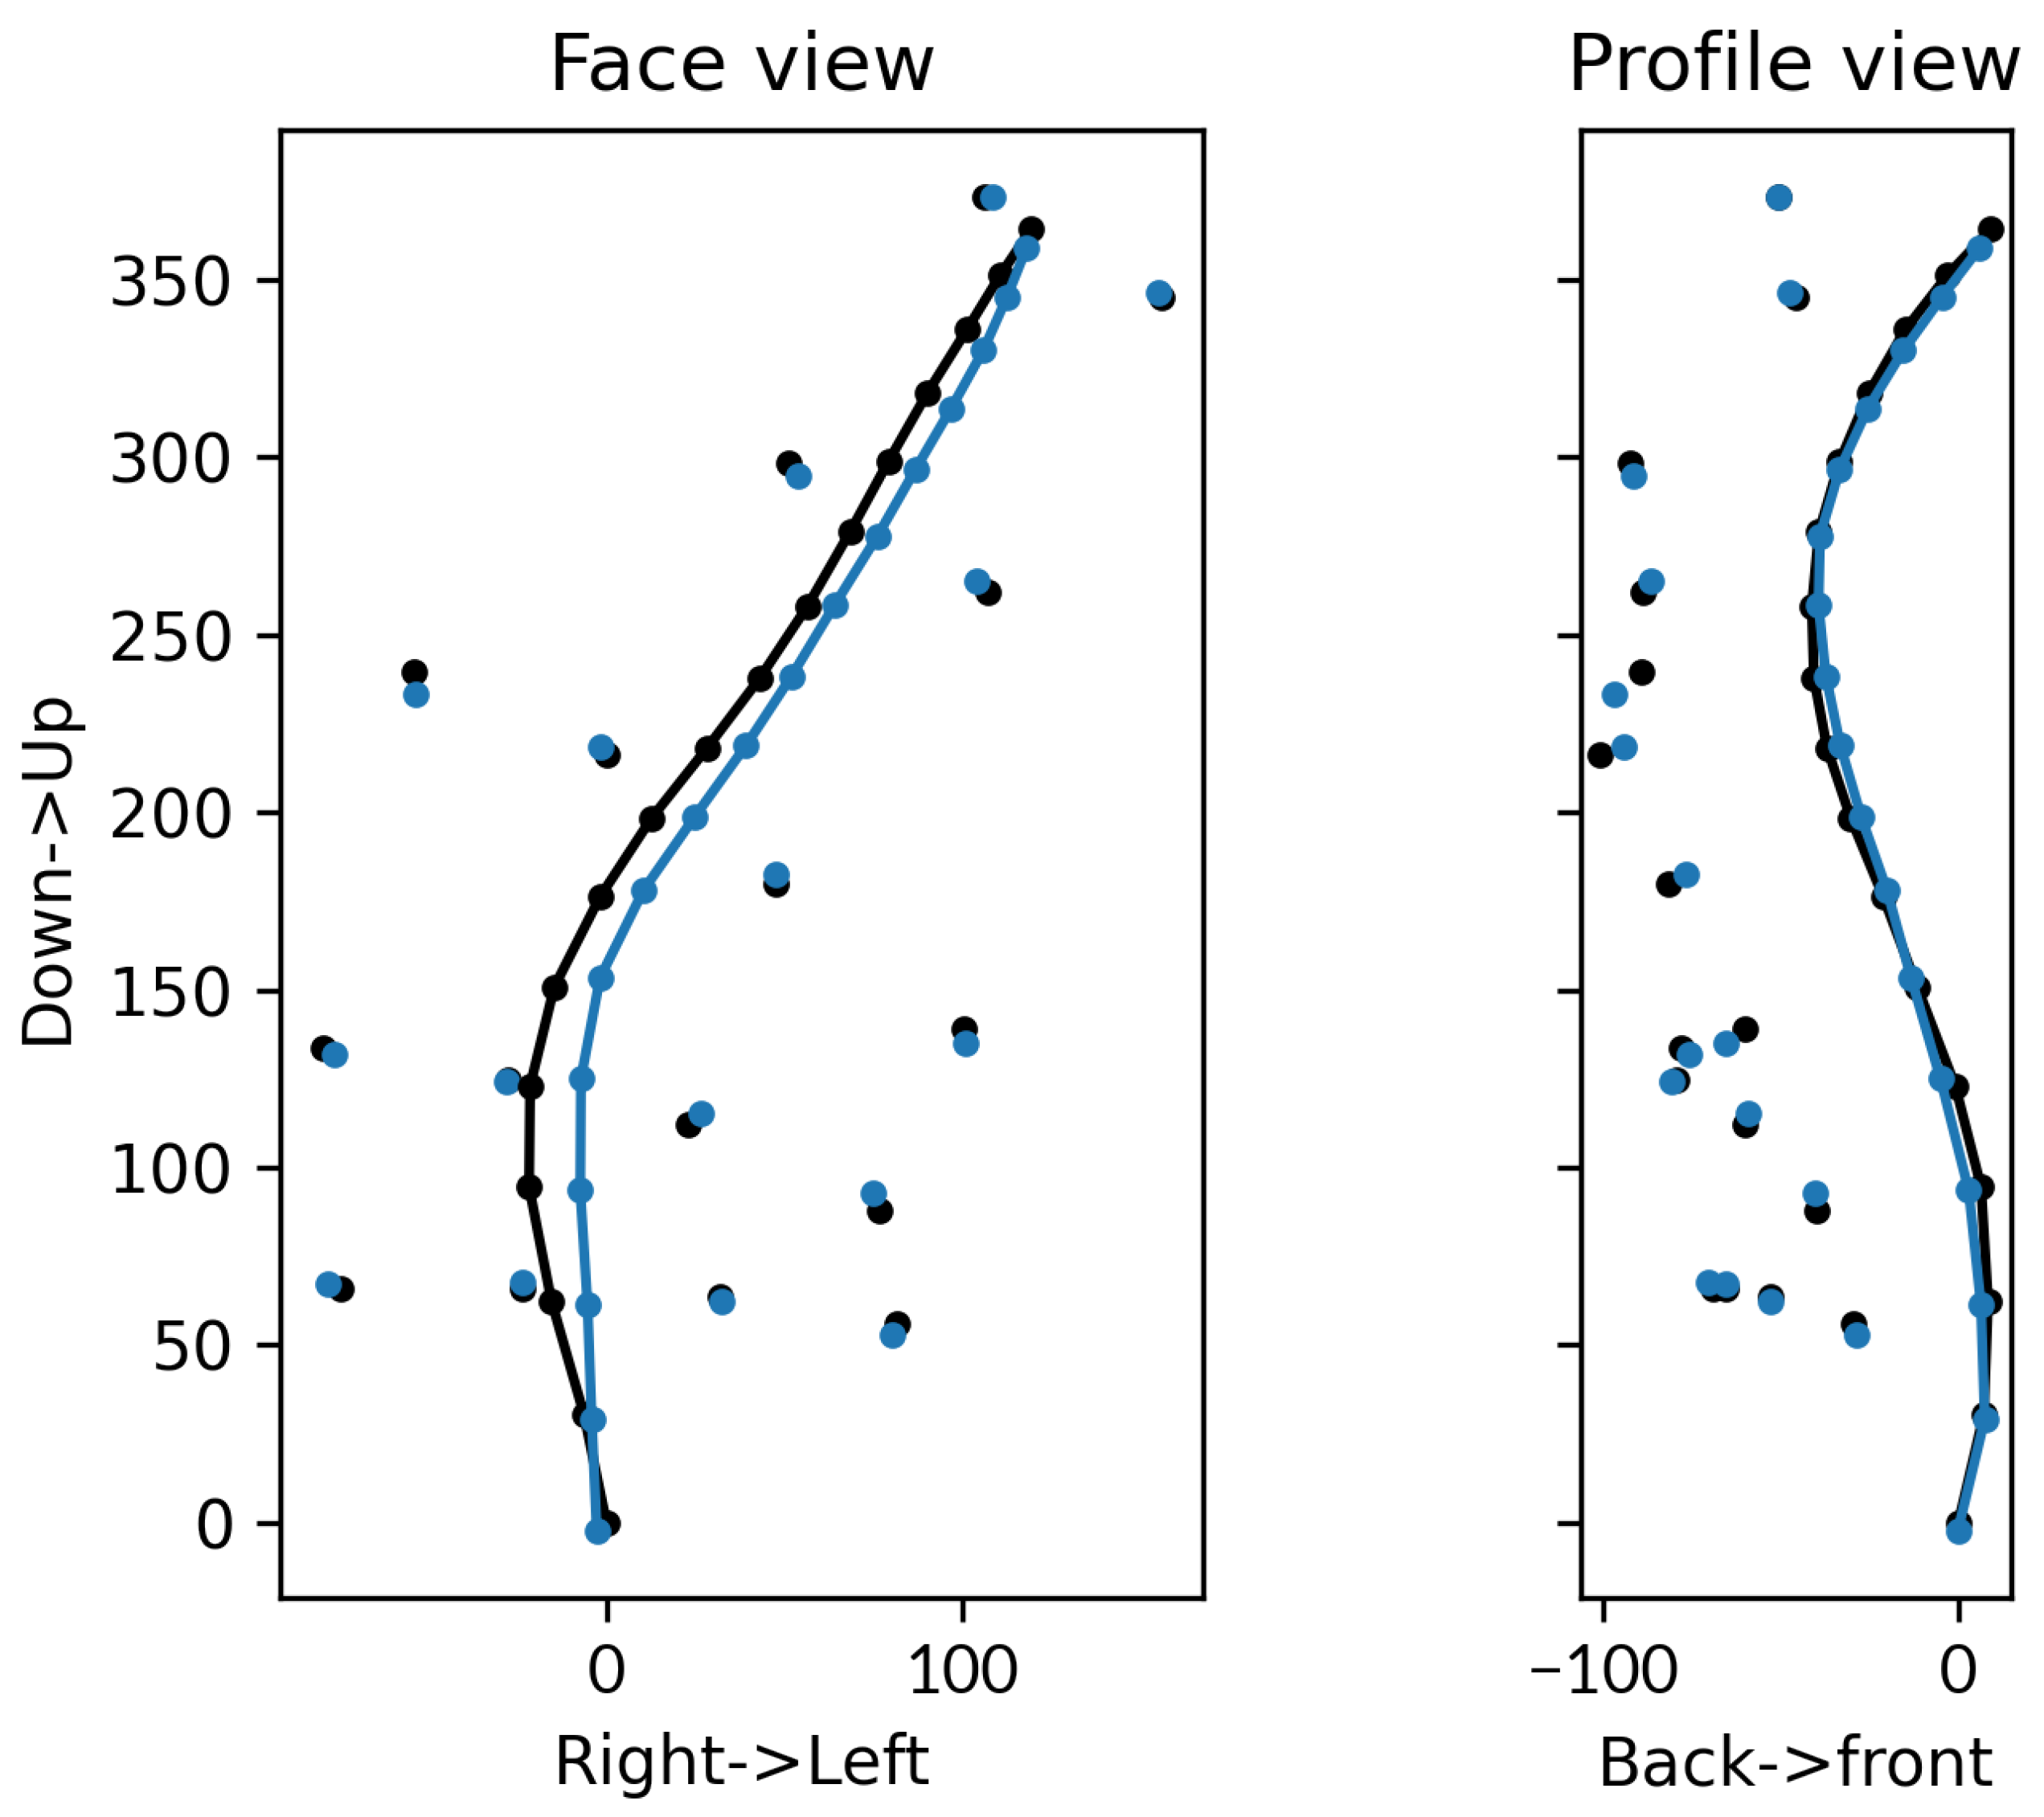

3.2. Accuracy of the Subject-Specific Model in Bending

3.2.1. External Accuracy

3.2.2. Internal Accuracy